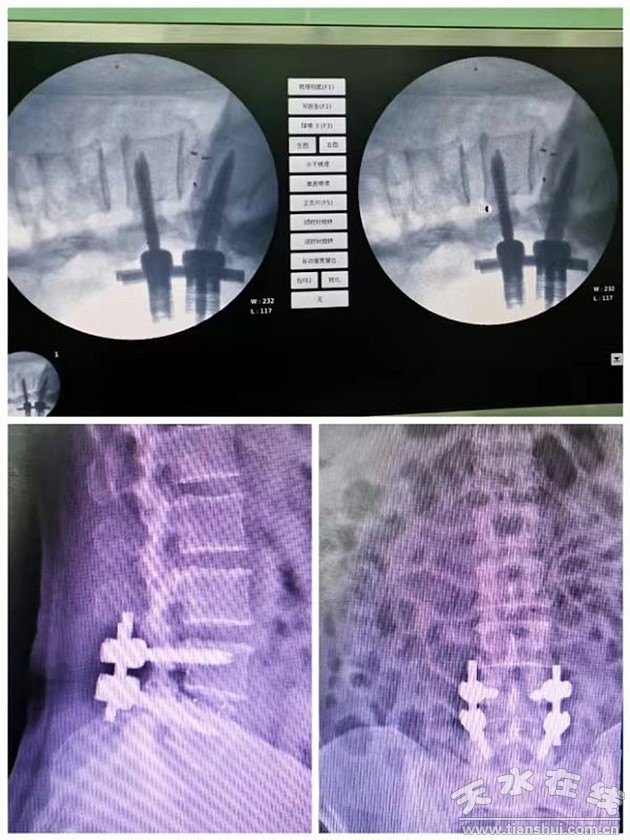

近日,骨科幫扶隊員郭虎兵醫(yī)生幫助縣醫(yī)院骨科再次開展了一項新技術(shù)——腰椎后路椎體間融合術(shù)(posterior lumbar interbody fusion ,PLIF),術(shù)后效果良好。據(jù)了解,該手術(shù)用于腰椎椎間盤突出癥并椎管狹窄的治療,也屬甘谷縣醫(yī)院首例。

郭虎兵醫(yī)生接診后,經(jīng)過詳細(xì)的診察,診斷為“腰椎椎管狹窄癥、腰4-5椎間盤突出、馬尾神經(jīng)受損”?紤]到患者病程長,癥狀反復(fù)發(fā)作,腰椎間盤突出并椎管狹窄,存在神經(jīng)根及馬尾神經(jīng)受壓的情況,建議手術(shù)治療。由于當(dāng)?shù)赜^念認(rèn)為腰椎手術(shù)風(fēng)險極高,手術(shù)后會癱瘓,患者及家人一度懼怕手術(shù),拒絕接受治療。郭虎兵醫(yī)生給患者及家屬耐心講解了疾病及手術(shù)情況后患者及家屬才欣然接受。手術(shù)前經(jīng)過充分的準(zhǔn)備,郭醫(yī)生精心設(shè)計了手術(shù)方案,打算給患者全麻下施行“腰4/5半椎板切除、PLIF”手術(shù)。10月10日,由郭虎兵醫(yī)生主刀為患者實施了手術(shù),手術(shù)過程順利。手術(shù)后患者腰痛及左下肢疼痛完全消失,左下肢乏力情況明顯減輕,左下肢及會陰區(qū)麻木減輕。術(shù)后第3天拔除引流管后患者帶護(hù)具下床活動,于術(shù)后第7天康復(fù)出院。

腰椎間盤突出癥并椎管狹窄癥為中老年人群比較常見疾病,可以導(dǎo)致神經(jīng)根、馬尾神經(jīng)損傷,患者會出現(xiàn)頑固性腰腿痛或間歇性跛行癥狀,甚至大小便功能異常,病程長,多反復(fù)發(fā)作,對患者日常生活產(chǎn)生嚴(yán)重影響。臨床治療主要包括保守療法與手術(shù)療法,保守療法主要采用藥物、推拿、按摩等方法,雖然身體損傷小,但治療見效慢、不徹底,整體療效不顯著。因此,大多數(shù)學(xué)者認(rèn)為,對于病程長、癥狀重的患者,一經(jīng)診斷明確,均應(yīng)采用手術(shù)治療,通過手術(shù)減壓來緩解神經(jīng)壓迫癥狀。但是手術(shù)可影響脊柱的穩(wěn)定性,傳統(tǒng)手術(shù)切除腰椎后部結(jié)構(gòu)引起腰椎失穩(wěn)發(fā)生率高,而郭虎兵醫(yī)生本次采用的“半椎板切除PLIF”手術(shù)方式,創(chuàng)傷相對較小,神經(jīng)減壓充分,并發(fā)癥少,能夠維持脊柱穩(wěn)定性且脊髓神經(jīng)功能恢復(fù)良好。而且,該手術(shù)應(yīng)用范圍廣泛,可用于腰椎滑脫癥、腰椎椎管狹窄癥、腰椎間盤突出癥、腰椎椎間關(guān)節(jié)不穩(wěn)等病癥的治療。